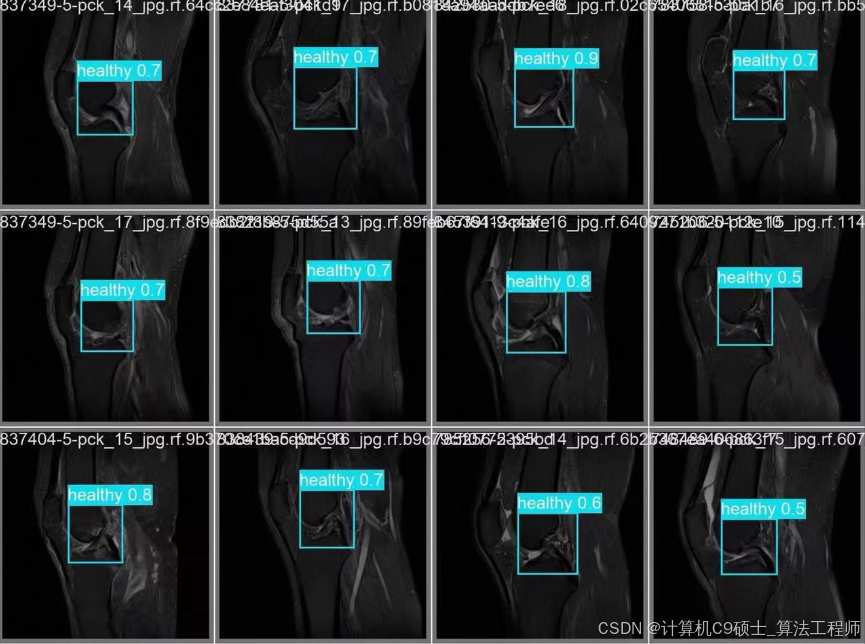

8. 可视化预测结果

使用以下Python代码来可视化模型的预测结果。

import torch

import cv2

import numpy as np

import matplotlib.pyplot as plt

# 加载模型

model = torch.hub.load('ultralytics/yolov5', 'custom', path='runs/detect/train/weights/best.pt')

# 读取图像

image_path = 'knee_injury_dataset/images/val/0001.jpg'

image = cv2.imread(image_path)

image = cv2.cvtColor(image, cv2.COLOR_BGR2RGB)

# 进行预测

results = model(image)

# 绘制预测结果

results.print()

results.show()